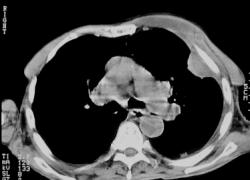

Отлично, коллеги, конечно, слева отграниченное скопление жидкости (за 4 дня значительно увеличившееся в объеме). Туберкулёз такую скорость не даст. Лейкоцитоз - в пользу гноя. Поскольку есть КТ, то логично его выполнить, прежде, чем пунктировать. КТ существенно дополнило общую картину, но некоторые вопросы остались. Прошу обратить внимание на топограмму и не обращать его на качество сканов (пошаговый томограф, скан 8мм, больной дыхание не задерживал),

Изображение Изображение Изображение Изображение Изображение Изображение Изображение Изображение Изображение Изображение Изображение Изображение Изображение Изображение Изображение Изображение Изображение Изображение Изображение Изображение Изображение Изображение Изображение Изображение Изображение Изображение Изображение Изображение Изображение Изображение Изображение Изображение Изображение

Увеличил наиболее принципиальные фрагменты сканов. Одиночная стрелка - пузырьки газа. Двойная стрелка - очаг деструкции в ребре (12мм).

Просто перелом, уже консолидированный. Движения правой руки почти в полном объеме, безболезненны. Больной травмы и переломы отрицает. Однако я за этот перелом зацепился, чтобы как-то объяснить скорость изменений слева. Впрочем, кому нужны объяснения, когда слева около 1л гноя? На гной указывают пузырьки газа.

По топограмме лучше не оценивать остеопороз (напряжение 133кV), хотя, конечно он есть, человек уже старческого возраста. Данный случай у меня оставил осадок неудовлетворённости. Пациент пробыл у нас менее суток. Найдя гной (на КТ), вызвали торакального хирурга из другой лечебницы. Он пропунктировал, задренировал, получил 1л. гноя и забрал пациента к себе. Остался не до конца выяснен механизм возникновения левосторонней эмпиемы. Я не успел больного посмотреть на УЗИ, а было бы интересно уточнить состояние мягких тканей 2-го межреберья слева, объем деструкции нижнего края преднего отрезка 2-го ребра. В конце-концов, теперь уже думаю, надо было сделать рентгенограммы поясничного отдела позвоночника. Пациент указывал на боль в нем. Думаю, что там могли оказаться свежие и, возможно, старые переломы.

У меня есть только одно предположение, хоть как-то объясняющее быструю отрицательную динамику рентгенологической картины. Думаю, что в результате травмы у больного нагноилась гематома мягких тканей левой половины грудной клетки(учитываю неизвестный перелом правой плечевой кости). На КТ на уровне 1-3 ребер слева определяется линзообразной формы отграниченное скопление жидкости, содержащей мелкие пузырьки газа (гной). Думаю, что именно его мы и видим на первом снимке " пристеночное затенение вне анатомических границ". Гной добрался до переднего отрезка 2-го ребра, а затем, частично разрушив межреберные мышцы, проник в грудную клетку. Вот здесь уже стала раздражаться и продуцировать много жидкости плевра. Жидкость смешивалась с гноем, кстати, при плевральной пункции гной был так жидок, что хорошо шел через тонкую иглу. Если предположение правильное, то слева эмпиема плевры "наизнанку", т.е. гной расположен экстраплеврально. Тому есть только косвенное подтверждение. Слева во втором межреберье отчетливо пальпировалось жидкостное образование, расположенное в мягких тканях (по КТ объём гноя в мягких тканях грудной стенки около 100мл). После установки дренажа в левую плевральную полость (а вернее, как я думаю, экстраплеврально), уже ничего не пальпировалось, что косвенно и указывает на наличие связи между двумя скоплениями жидкости. Думаю, что именно здесь (на этом скане, где видна деструкция нижнего края 2-го ребра) и сформировалась своеобразная "запонка", добравшаяся до плевры и вызвавшая такую скорость формирования эмпиемы. Это мое предположение, возможно, есть другие мнения. На самом деле первоисточником может быть остеомиелит ребра, правда, слишком велика диспропорция между объемом деструкции и количеством гноя (даже в мягких тканях грудной клетки). Но и тогда эмпиема тоже эстраплевральная. В любом случае, было что обсудить. Спасибо за высказанные мнения.